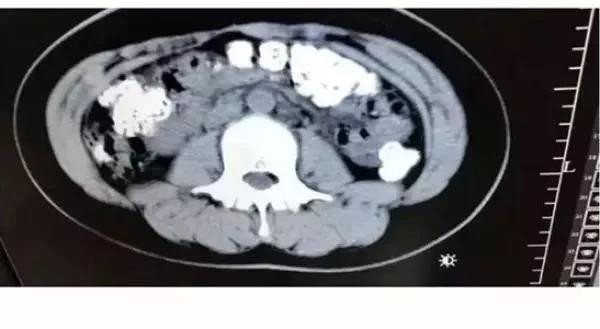

Phát hiện bụng cô bé phình to bất thường, các bác sỹ đã quyết định đưa bệnh nhân này đi chụp cắt lớp. Kết quả chụp cắt lớp cho thấy hàng trăm vật thể nhỏ hình tròn nằm trong khắp các cơ quan nội tạng, từ dạ dày, đại tràng, ruột và hậu môn.

Sau khi cùng nhau thảo luận, các bác sỹ kết luận những vật thể nhỏ này là các hạt trân châu chưa được tiêu hóa hết. Bác sỹ Zhang Louwei đã hỏi cô bé xem bệnh nhân có ăn gì khó tiêu trong vài ngày qua hay không. Cô bé thừa nhận đã uống một cốc trà sữa từ 5 ngày trước khi nhập viện.

Phát hiện hàng trăm hạt trân châu chưa tiêu hóa trong bụng một cô bé ảnh 2Các hạt trân châu vẫn mắc kẹt trong hệ tiêu hóa. (Ảnh: 9GAG)